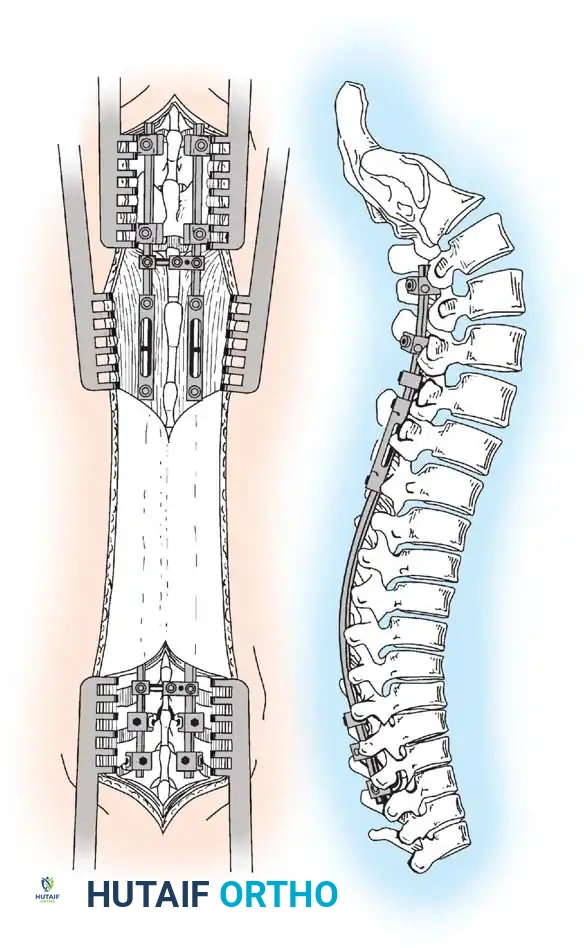

Technique of dual-rod instrumentation showing anteroposterior and lateral views. The construct is carefully contoured to maintain sagittal alignment, with extended tandem connectors placed in the thoracolumbar spine to minimize soft-tissue profile.